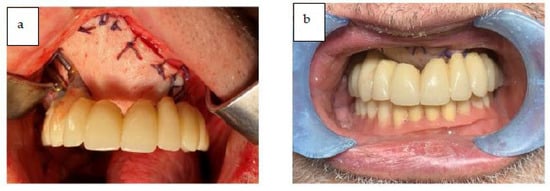

After the reconstructive phase with the ALT flap was completed, the patient had the provisional prosthesis placed, and left the operating room with rehabilitation completed in one day. The fixed provisional prosthesis was delivered to the patient on the day of the surgery (Figure 15).

Figure 15.

(a,b) The provisional prosthesis in occlusion.

The occlusion and prosthesis were checked at a follow up on the 7th post-operative day. The patient underwent a cycle of radiotherapy without any complications or dehiscence of the flaps. The final fixed prosthesis was delivered 8 months after the surgical intervention. The definitive final removable prosthesis was retained by an implant-supported titanium bar that allowed the patient to have a strong and stable occlusion during function and provided easy access for oral hygiene. The patient reported a complete satisfaction from phonetic, functional, and aesthetic points of view. Figure 17a–d shows the final prosthesis (Note on Figure 17: The evolution of the oro-naso-sinusal defect repair through the soft tissue graft was uneventful without any complications. As can be seen in Figure 17, the tissue was œdematic for the first weeks and slowly shrank to healthy dimensions after healing).

Figure 17.

(a–c) Intra-oral occlusal and frontal view of the titanium bar retaining the definitive prosthesis and final prosthesis in occlusion. (d) Panoramic X-ray showing final prosthetic rehabilitation in place.